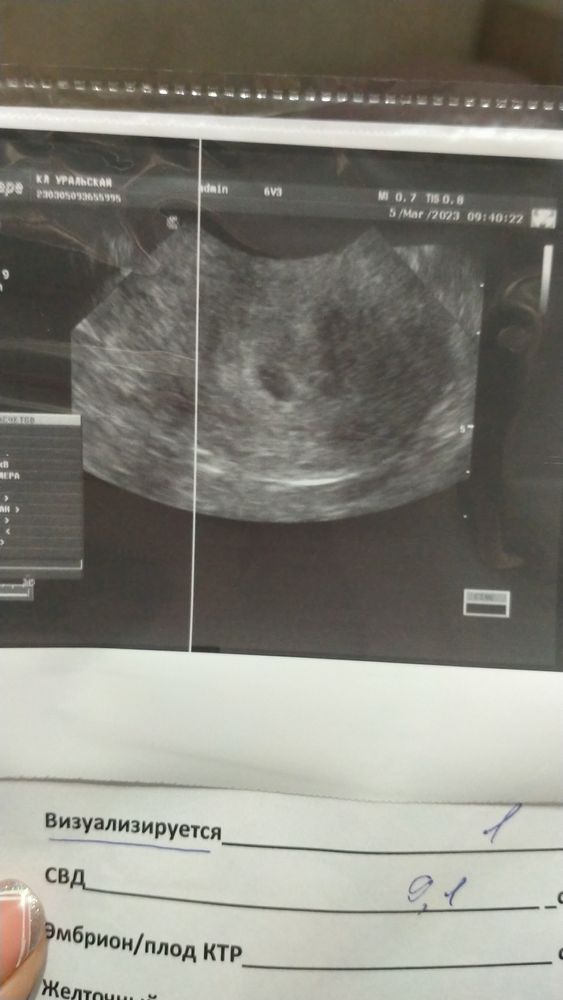

Эля, а когда вы пошли на узи? У меня просто также за 10 дней примерно до задержки тест начал призрак показывать. Хгч вырос с 122 до 442 за два дня, завтра ещё раз хочу сдать, очень боюсь что будет бхб. Так как по сути задержки то ещё нет, месячные 26-27 должны прийти, страшно…впереди два страшных дня)))

Ксения, получается через день предполагаемых месячных уже была на УЗИ